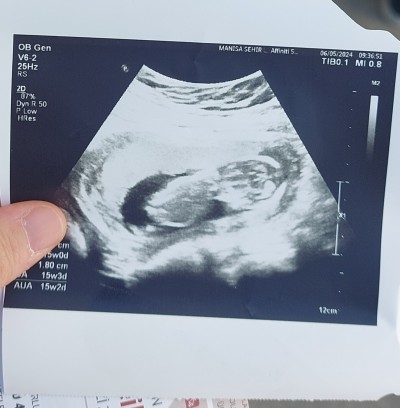

Merhaba güzel anneler 16 hafta gebeyim ulturason 15 haftalik cinsiyet tahmininde bulunabilir misiniz?

Canım resim tam belli olmuyor ki nasıl tahmin edelim ama içimize hangisi doğsa onu deriz heralde ben erkek diyorum ☺️

Kiz gecti icimden

Kız gbi ya:)

erkek geçti içimden

Kiz gibi hayirlisi İnşallah